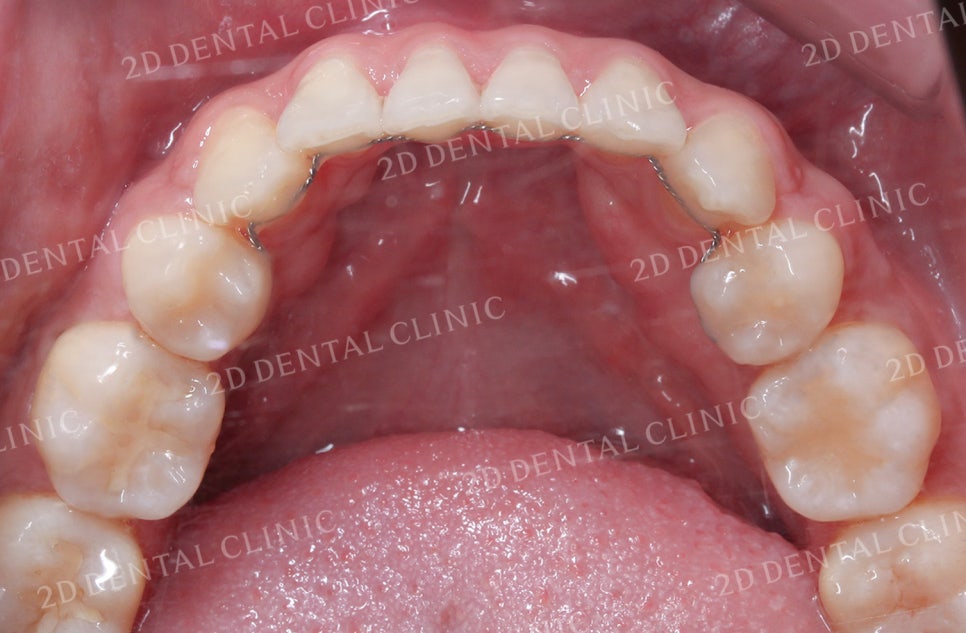

<하악 설측면 사진> <상악 설측면 사진>

상악과 하악의 설측면 사진입니다.

하악의 경우 전치부의 좁은 공간으로 인해

총생이 발견되는데요,

상악 역시 치아가 올바르게 배열되기에

충분한 공간이 확보되지 못한 상태입니다.